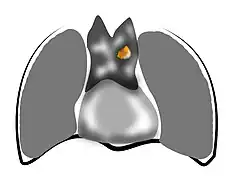

- Aspect scannographique

Présentation tomodensitométrique classique d'un thymome à un stade précoce (cercle rouge). À l'arrière, l'aorte, la veine cave supérieure et l'artère pulmonaire sont visibles en coupe.

Présentation tomodensitométrique classique d'un thymome à un stade précoce (cercle rouge). À l'arrière, l'aorte, la veine cave supérieure et l'artère pulmonaire sont visibles en coupe. Scanner injecté, en fenêtre médiastinale, montrant un carcinome thymique envahissant les structures médiastinales :